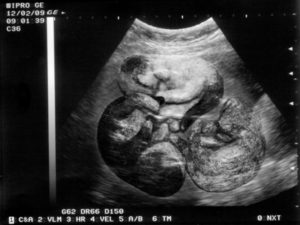

К пятой неделе с помощью УЗИ ветеринар определяет, сколько котят вынашивает кошка и течение беременности.